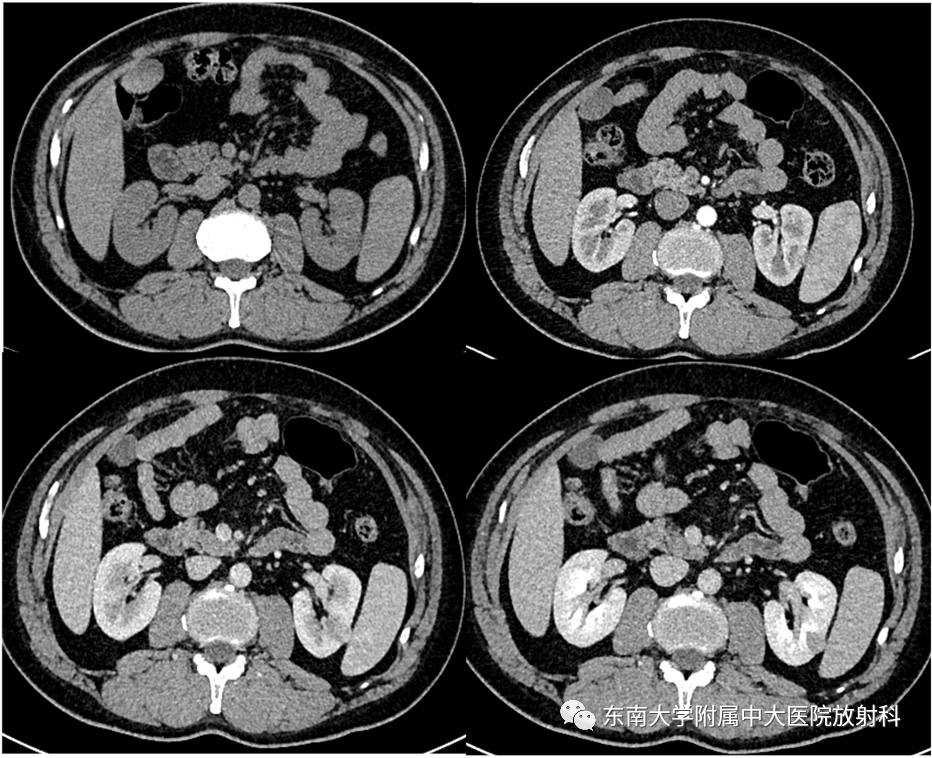

病例1

•男,46岁

•主诉:因“咽部不适3月”入院。入院胸部CT提示发现肾脏占位。